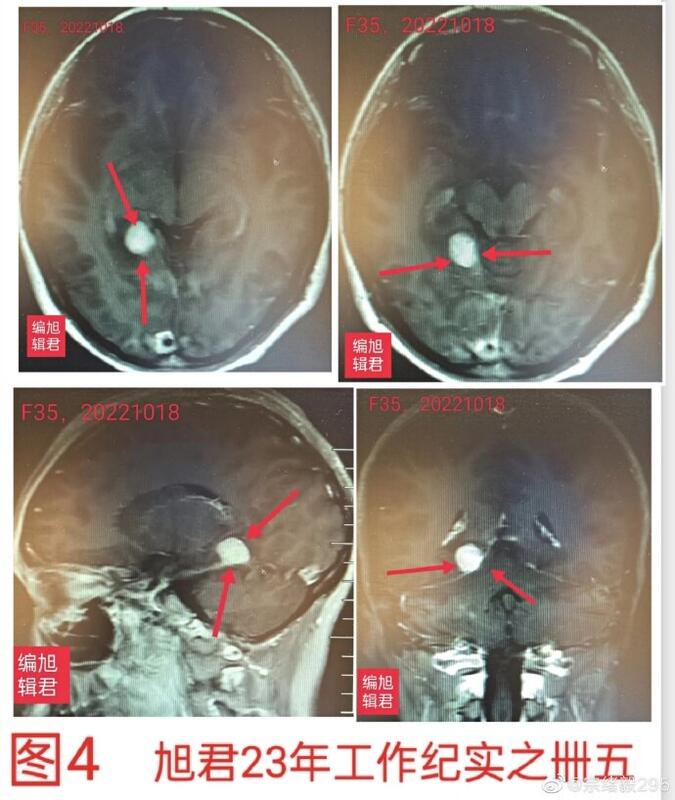

图4:某患者35岁,体检发现,无不适。

图-4